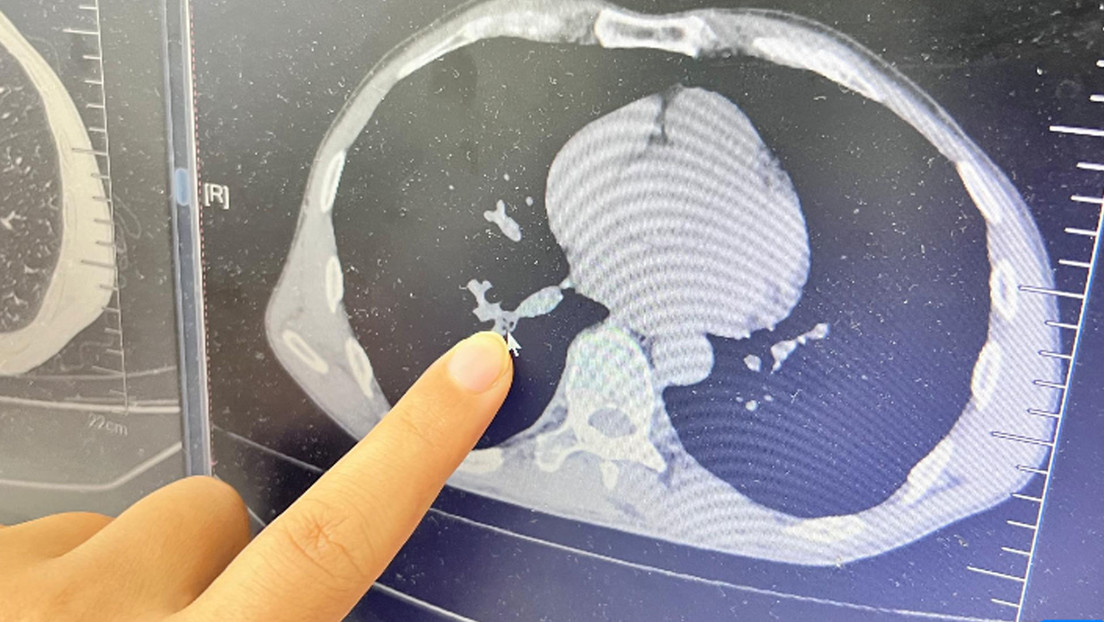

Después de una inspección inicial, el médico especialista en otorrinolaringología Lin Ling determinó que el cuerpo extraño podía estar alojado en sus vías respiratorias inferiores. La exploración del tórax reveló algo raro en su pulmón derecho. Al día siguiente, el paciente fue sometido al procedimiento quirúrgico bajo anestesia local y el equipo médico pudo identificar y extraer la cucaracha envuelta en abundante flema.